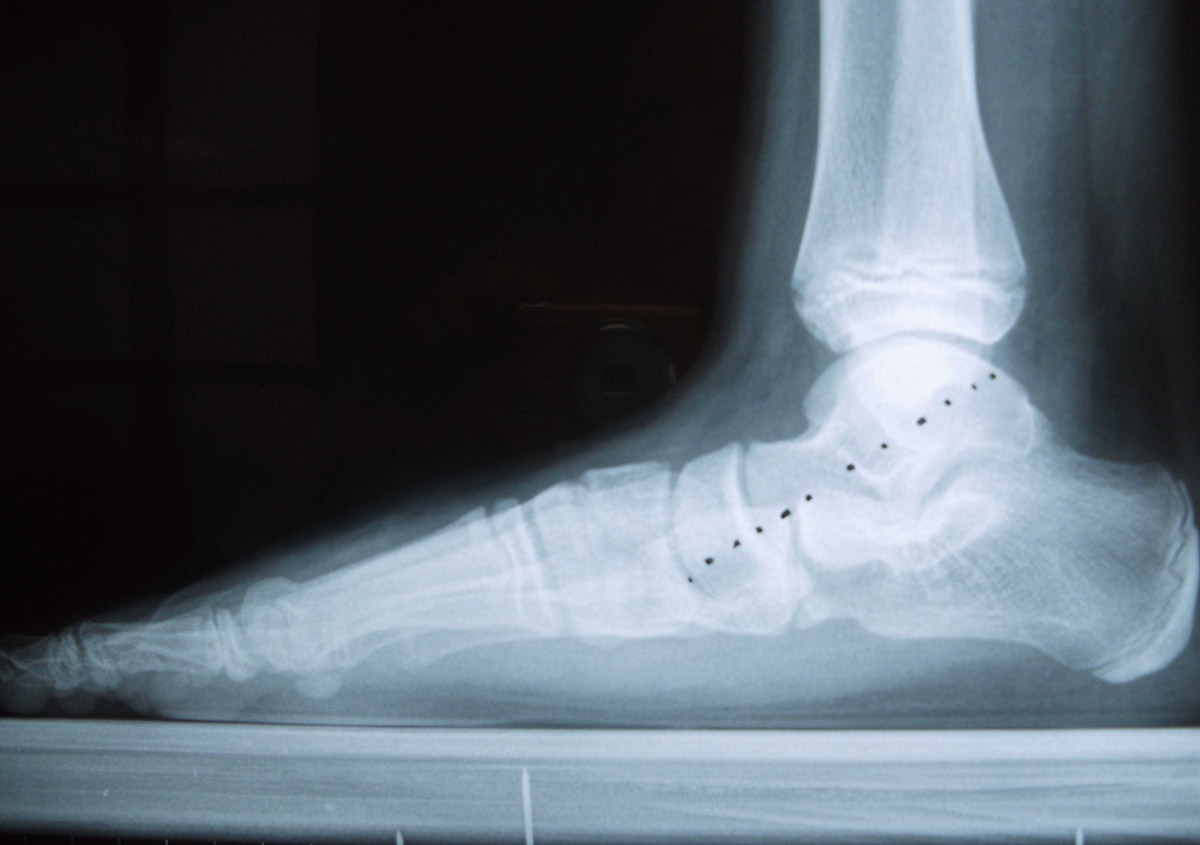

piede piatto di bambino

Con un intervento mini invasivo si può oggi correggere anche un piede gravemente piatto: è consigliabile intervenire ad accrescimento non ultimato (l’ideale è intorno ai 9-10 anni), anche se nel caso presentato il paziente, pur avendo eseguito la prima radiografia a 12 anni, ha ritardato l’intervento di 2 anni.

Fig. 1 Radiografia preoperatoria del piede destro che evidenzia come l’astragalo sia “disallineato” (linea tratteggiata) rispetto al resto del piede. Questo accade perchè l’astragalo tende a verticalizzarsi e a protrudere all’interno del piede, facendo cadere la volta plantare e dando l’immagine tipica del “piattismo”.